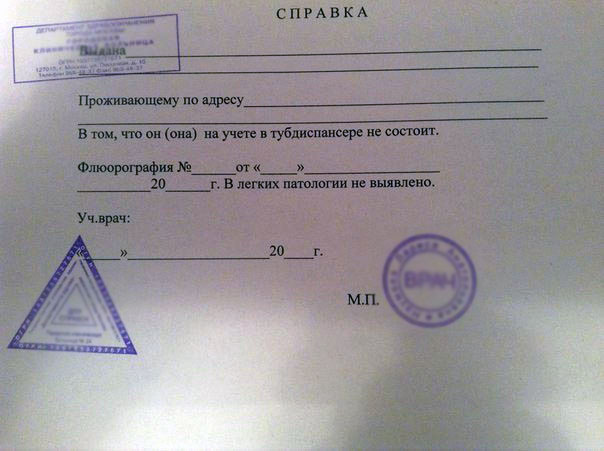

Фотографии рентгеновских снимков без необходимости направления от врача